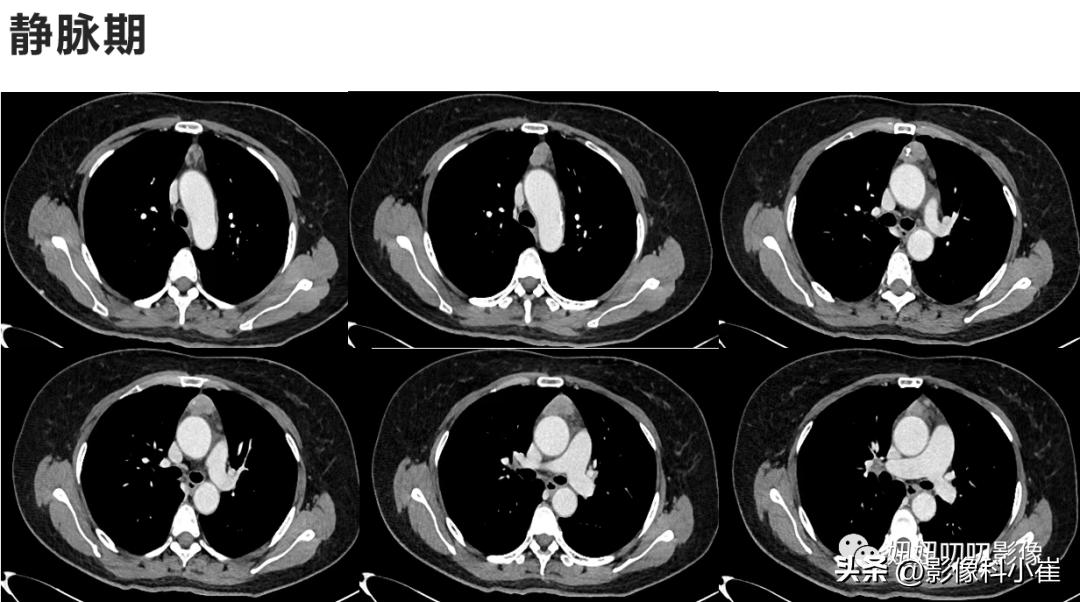

前纵隔见一类椭圆形软组织密度灶,边界尚清,截面约3.3X1.9cm,内见点状钙化灶,增强扫描呈中度不均匀强化,内见条形弱强化分隔,后缘紧贴升主动脉,病变周围脂肪间隙见条索状高密度灶,其左后方另见一小结节灶,边界清,大小约1.1X0.6cm,增强扫描呈轻度强化。双肺下叶见微小结节灶,边界清,直径约0.2-0.3c。右肺上叶尖段见囊状无肺纹理区,边界清,大小约1.5X1.0m。右肺上叶另见少许索条灶,边界清。部分支气管壁略增厚,段及段以上支气管通畅。纵隔及双肺门未见明显增大淋巴结。双侧胸腔未见明显液体密度灶。

A:主要就看见了个钙化,查体发现,可见裂隙样低密度弱强化,胸腺瘤?CD?一般见条状强化,异位甲状腺?畸胎瘤? 倾向畸胎瘤。

B:裂隙样低密度弱强化,一般提示胸腺瘤,并且没有脂肪,50多岁了还杀畸胎瘤了。

①:病理是胸腺瘤;

②:你看钙化,往往点状倾向胸腺瘤,蛋壳样、条状倾向畸胎瘤,前纵隔的小孩还要记得生殖细胞瘤(AFP很高)